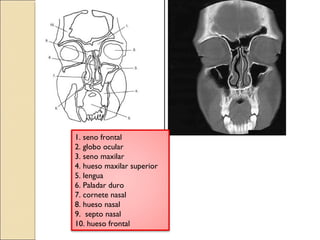

1. seno frontal

2. globo ocular

3. seno maxilar

4. hueso maxilar superior

5. lengua

6. Paladar duro

7. cornete nasal

8. hueso nasal

9. septo nasal

10. hueso frontal